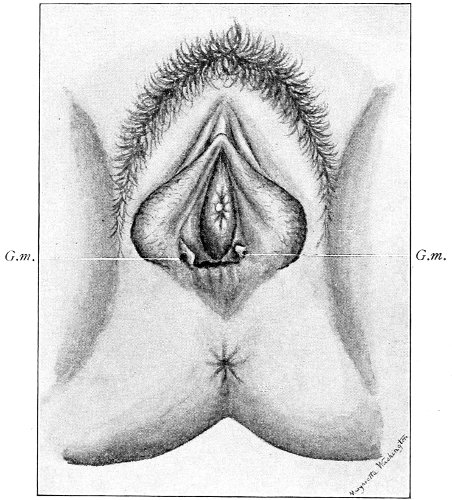

Fig. 16.—Appearance of the external genitals in a woman with gonorrhea: G. m., gonorrheal macula situated at the base of a vaginal caruncle.

Suppuration of the duct may be demonstrated by pressing over the course of the duct, when a drop of pus will escape from the opening. In such cases the orifice of the duct is usually surrounded by a red areola, resembling a flea-bite, which has been called the gonorrheal macula (Fig. 16). This macula persists long after all other traces of inflammation about the vulva and vagina have disappeared, and after all frank suppuration in the duct has subsided. Its presence indicates at least the probability of previous gonorrheal infection.

Suppuration of the vulvo-vaginal gland is accompanied by marked swelling and peripheral edema. The swelling may extend to the anus, and is of characteristic shape (Fig. 17). The pain is always severe. Fluctuation is first apparent on the inner surface of the labium majus. If the condition is not treated, one or more fistulous openings appear below the orifice of the duct, and the pus is discharged. The condition then becomes chronic. The fistulous openings persist. Acute inflammation disappears from the gland, leaving it in a condition of hypertrophic induration. A thin, milky or greenish, purulent fluid may be pressed out of the duct or the fistulous openings. Infection from this discharge may be communicated to man, or may ascend the genital 40 tract, producing inflammation of the endometrium or of the Fallopian tubes.

Fig. 17.—Abscess of right vulvo-vaginal gland.